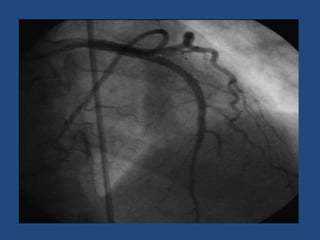

5 semanas después

A los 2 meses

•   Disnea CF I habitual

•   Holter 24 hs sin arritmia ventricular

•   TAS 85-97 habitual

•   TAD 54 a 63 mmhg

MC: epigastralgia intensa de 2 días de evolución